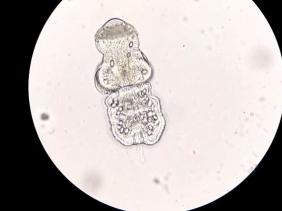

Ngay sau ca phẫu thuật, TS.BS Trần Thị Huệ Vân - Trưởng bộ môn Vi sinh - Ký sinh, Đại học y Dược TP. HCM tiến hành xét nghiệm nang sán. Hình ảnh thu được cho thấy sán vẫn còn sống, kết quả định danh là sán dây chó thuộc giống Echinococcus.

Sán dây chó còn sống sau khi bóc tách nang và gửi đi xét nghiệm. Ảnh: Vietnamnet.